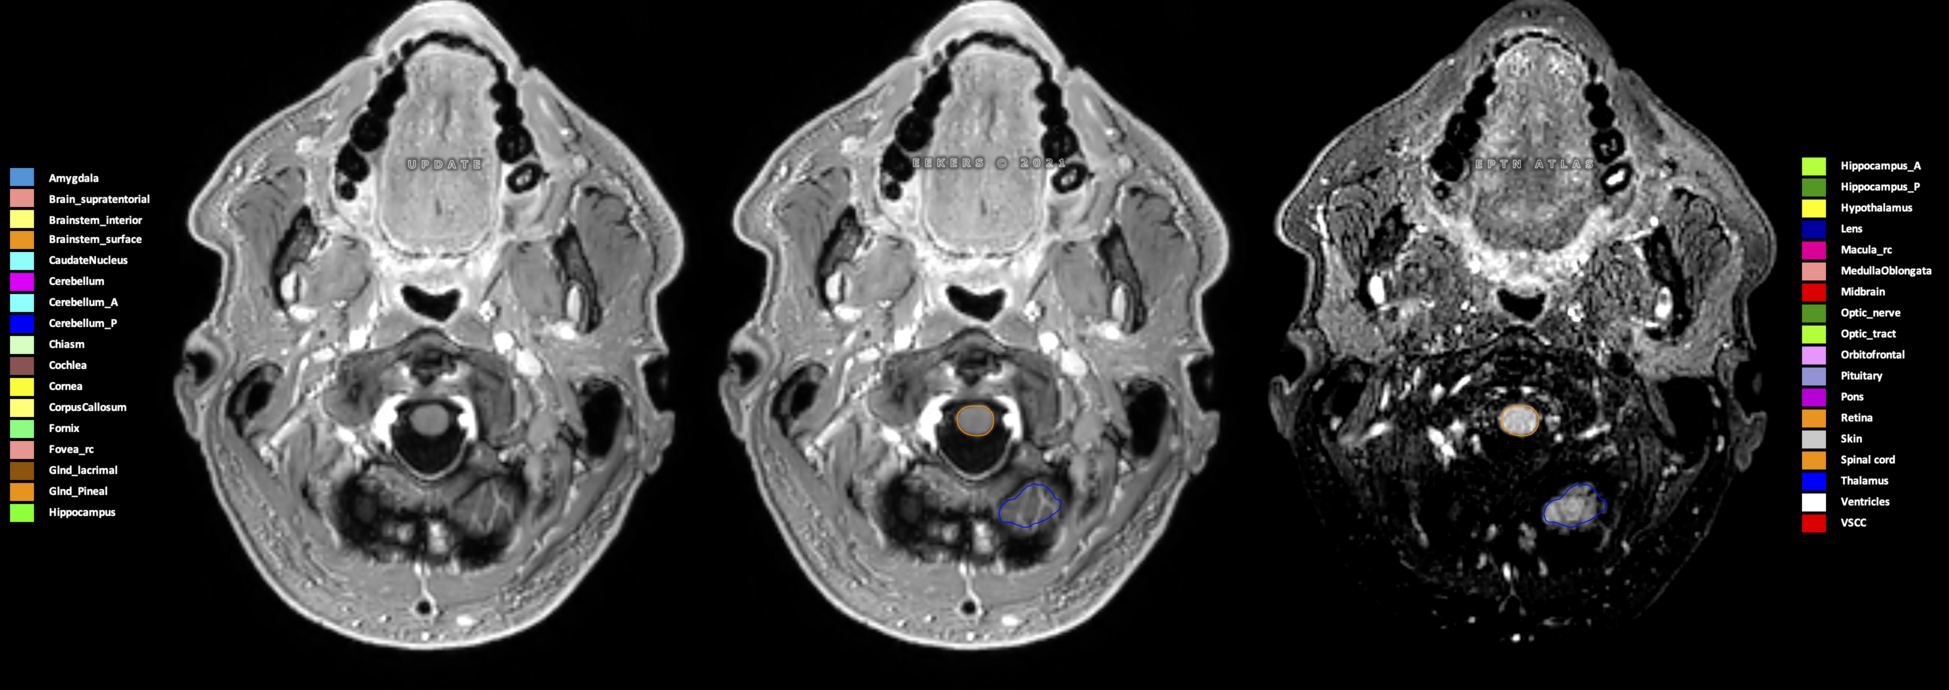

Eekers et al. have published an international neurological atlas for contouring of organs at risk in consensus with the European Particle Therapy Network (EPTN) in 2018 and an update in 2021. The purpose of this consensus atlas is to decrease inter- and intra-observer variability in delineating OARs relevant for neuro-oncology.

Included are all OARs known to be relevant for radiation-induced toxicity in neuro-oncology: brain, brainstem (midbrain, pons, medulla oblongata), chiasm, cerebellum (anterior & posterior), cochlea, cornea, hippocampus (anterior & posterior), hypothalamus, lens, lacrimal gland, optic nerve, pituitary, skin, and vestibular & semicircular canals. To further facilitate research on cognition, vision and radiological changes after irradiation of the brain, potential clinically-relevant OARs are included: amygdala, caudate nucleus, cerebellum (anterior & posterior), corpus callosum, fornix, macula, optic tract, orbitofrontal cortex, periventricular space (PVS), pineal gland, and thalamus.

Three-dimensional delineation of the 25 consensus OARs for neuro-oncology are shown on CT (WW/WL 120/40, 3000/600), 3T MR images, (T1Gd, T2FLAIR 1mm) and 7T MR (MP2RAGE 0.7 mm). All are presented in transversal, sagittal and coronal view.